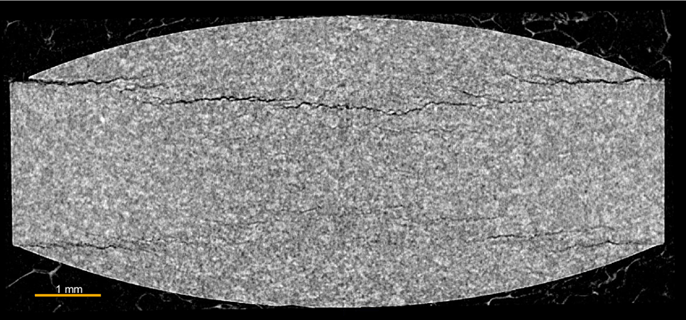

錠剤をながめてみても、どこにどのような形の欠陥があるのかはわかりません。このような場合あらかじめ欠陥の部位を切断し、顕微鏡観察することは困難ですが、3次元化されたデータを切り取りながら観察すれば、欠陥の位置がわかります。図2には錠剤内部のクラックの断層画像を示します。このようなクラックが錠剤の中心になかったとしても、X線CTならば見つけることができます。

図2:錠剤内部のクラックの観察例(断層画像)